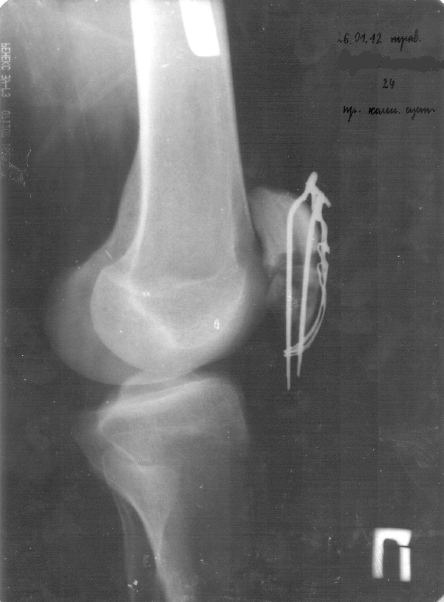

всё зависит от того, как сращиваться будет, каждый месяц со фотографиями появляюсь, они смотрят. вообще пол года примерно сращение идёт, но это всё индивидуально,

сегодня только два мес. как кости свели друг к другу. вобще "бывалые" говорят что долгая история, типо пару лет минимум будещь так мучиться, х.з. откуда такие прогнозы конкректно ко мне. вообще в больнице столько нытиков, послушаешь так писец, я никогда не слушал, настрой всегда только на позитив, как бы хреного и устрашающе не было, даже во сне брёл - "всё будет за и бись!" Но и позавидовать терпеливости некоторых тоже можно было. Я лежал в таком отделении, где были люди все в железе, смотреть дурно, мы с тобой ещё "счастливые" люди по сравнению. кстати мысли вроде как материализуются, так что только только не падай духом, товарищ по несчастью. И на нашей улице камаз с водкой перевернётся! (с).